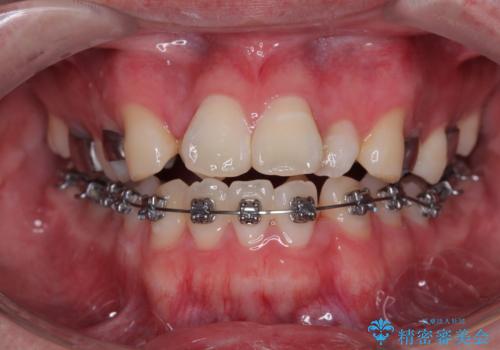

1年でここまで変わる!歯列のがたつきと正中のズレを改善した矯正治療(メタルブラケット×MARPE)

適切な診断と装置の選択により、1年という短期間でここまで改善できます。